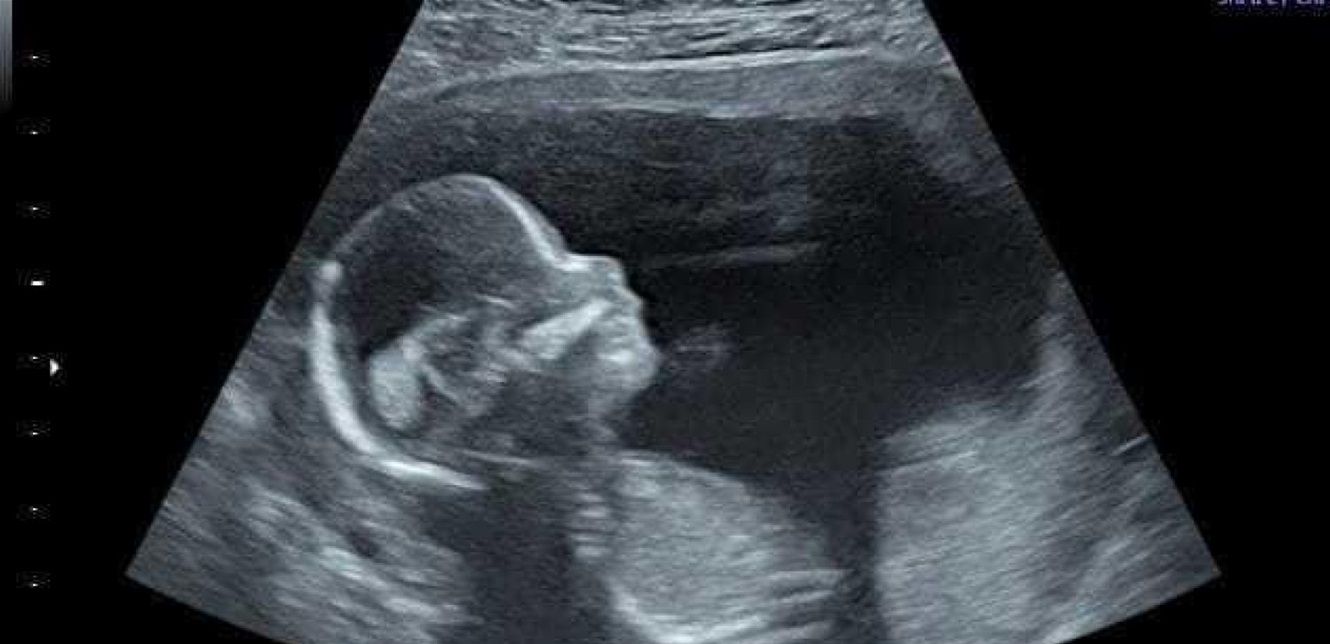

وكانت الأبحاث السابقة أظهرت أن الأطفال الذين ما زالوا في الرحم (ابتداء من عمر سبعة أشهر تقريبا) يمكنهم سماع حديث أمهاتهم.

ويمكنهم أيضًا سماع أصوات أخرى، مثل الموسيقى والضوضاء العامة و التعرف على صوت أمهم بعد الولادة وألحان محددة تتعلق بكلامها.